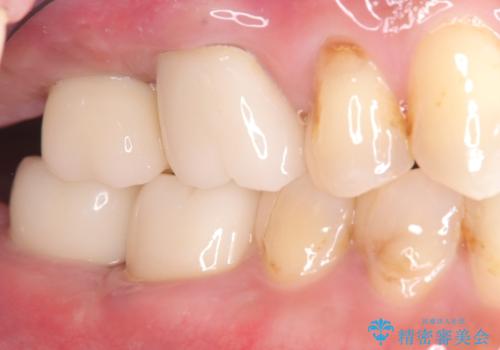

まず、右上6・右下6の根管治療を再度行い、根の状態をしっかり整えた上で、セラミッククラウンを装着しました。さらに、欠損していた右上7・右下7にはインプラントを埋入し、セラミッククラウンを装着。治療後は、「奥歯でしっかり噛めるようになり、不安なく食事ができるようになった」と患者様にも大変ご満足いただきました。